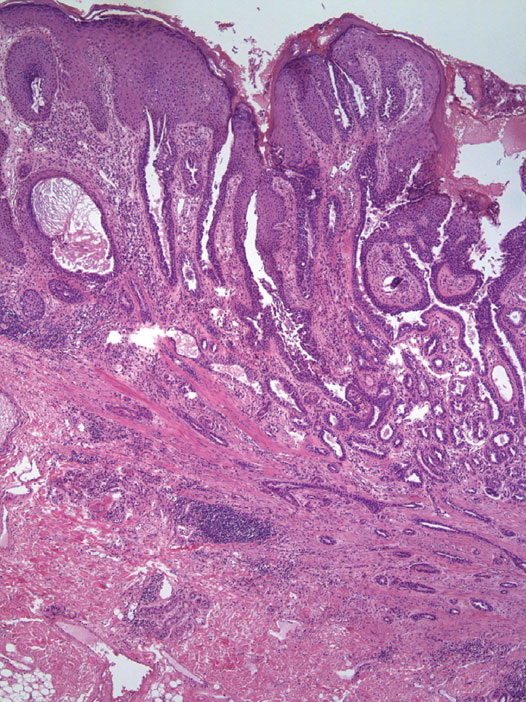

Syringocystadenoma = غدوم كيسي عرقي